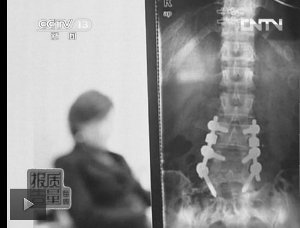

教练按压导致学员腰椎间盘突出。(央视截屏)。

无独有偶,练习瑜伽受伤的现象,近几年经常出现在报道中。2011年,湖北一位女士因为练瑜伽遇到水货教练,竟然大腿骨折,最终瑜伽馆承担赔偿责任;2010年,上海的郑女士练瑜伽时,因为教练按压而导致腰椎间盘突出,如今,4颗合金钢钉永远埋在她第4、5节腰椎上(图1)。